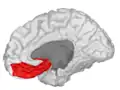

Medial surface of cerebral cortex - gyri -

Basal surface of cerebrum. Orbital gyrus shown in red. -

Medial orbitofrontal cortex, inner slice view -